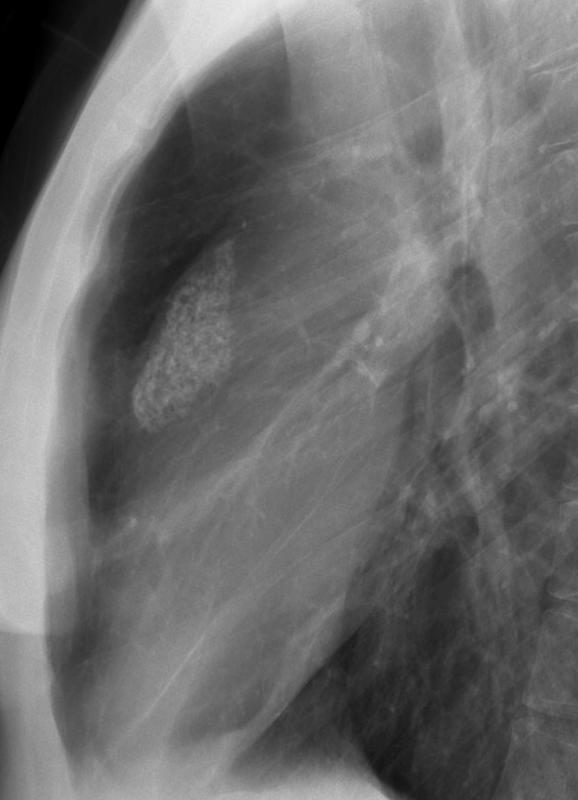

Gallery Mediastinum Lymphoma Radiated nodes (Hodgkin's)

Radiated nodes (Hodgkin's)